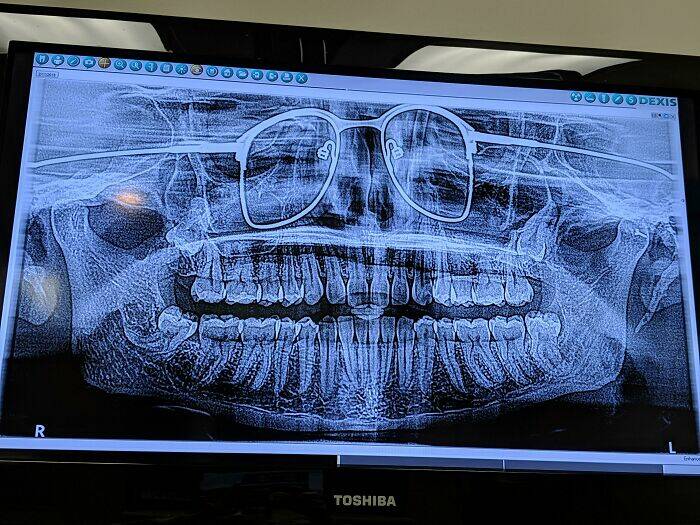

"I Got A Panoramic Xray Of My Teeth The Other Day. The Dentist Forgot To Have Me Remove My Glasses"